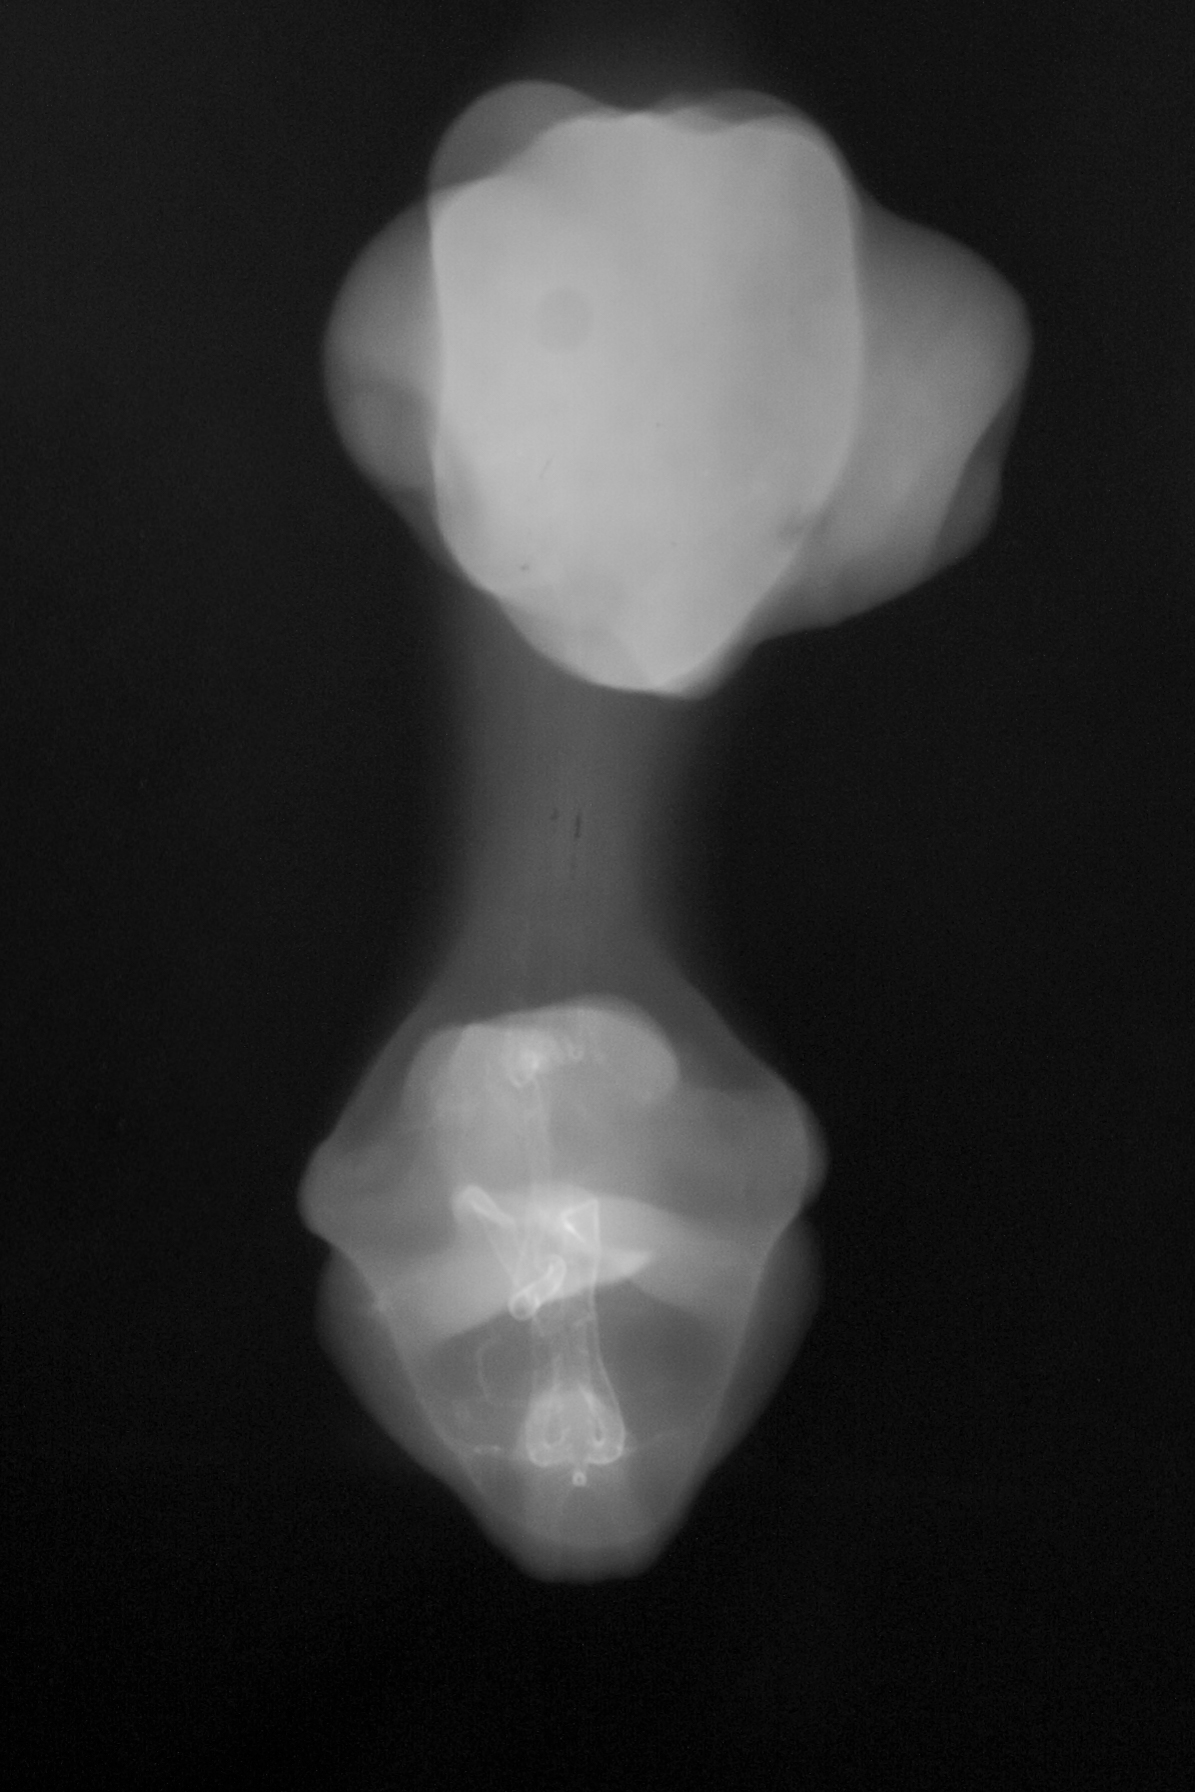

Chick Embryo Microangiography

Hamburger-Hamilton (HH) Stage 31 (approx. 7 days)

X-Ray Micrographs